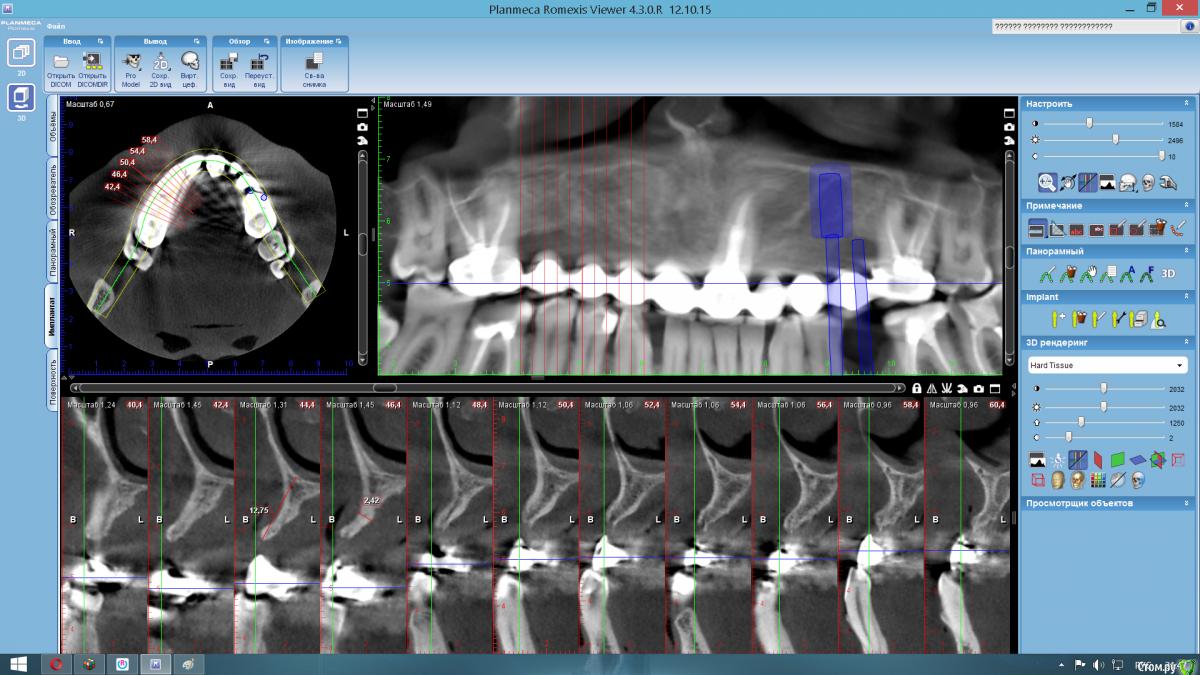

Nazim_NV86 Опубликовано 17 ноября, 2016 Поделиться Опубликовано 17 ноября, 2016 Коллеги, вот такой вам случай. Коронкам лет 20. Стоят и судя по всему и будут стоять дальше. Варианты костной пластики? Блоки, мембрана-пины, титановая сетка ... Тема актуальная. Буду дополнять со временем результатами. Ссылка на комментарий

pit Опубликовано 18 ноября, 2016 Поделиться Опубликовано 18 ноября, 2016 Я бы одномоментно установил бы как минимум в позиции 15 и 11 зубов. И позиционировал бы, и аугментировал гребень в небном направления (исходя из соотношения дефекта и положения старых коронок). Метод и материал аугментации: кортикальная мембрана(ламина) с фиксацией швами или титановая мембрана и 2-3 пина. Графт: ксено+ауто( сколько бы собрал рядом. С вестибулярной стороны при необходимости ССТ( вторым этапом). Ссылка на комментарий

Nazim_NV86 Опубликовано 18 ноября, 2016 Автор Поделиться Опубликовано 18 ноября, 2016 Я бы одномоментно установил бы как минимум в позиции 15 и 11 зубов. И позиционировал бы, и аугментировал гребень в небном направления (исходя из соотношения дефекта и положения старых коронок). Метод и материал аугментации: кортикальная мембрана(ламина) с фиксацией швами или титановая мембрана и 2-3 пина. Графт: ксено+ауто( сколько бы собрал рядом. С вестибулярной стороны при необходимости ССТ( вторым этапом).Ламинами пока не работал, но прикупил одну. Как её ушить пока не понимаю. Пины наверно не достанут, но винты должны. Ссылка на комментарий